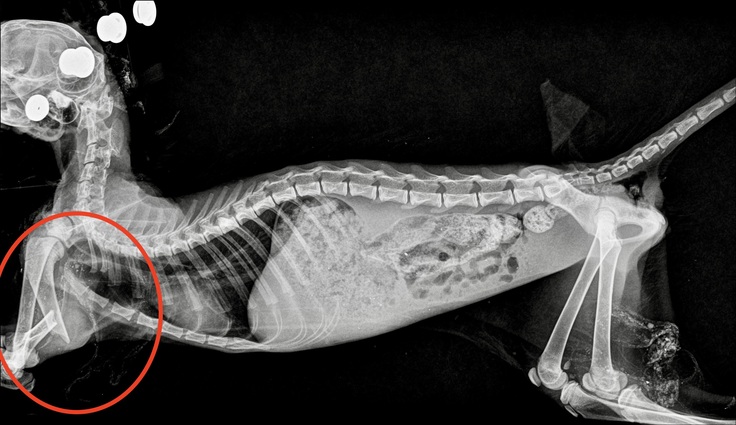

◯上げていた前足部分は左上腕骨骨折でした。 最初の病院でもセカンドオピニオンの病院でも確認していただいたところ、やはり固定だけではちゃんと歩けなくなる可能性が高い場所だとの診断でした。いつ骨折したかわからないということもあり早く決断をした方がいいと言われましたがとてもとても悩みました。

子猫の年齢や体重を考えて手術はしない選択をしたかったのですが、局所麻酔で骨の位置を戻して固定をする方が子猫が怖がって危険で、固定ではしっかり治すことが難しい部分だという説明もあり、手術をしていただくという判断をしました。

1週間〜2週間に1度レントゲンで状態を確認しています。 外からピンを固定する方法を希望していましたが、手術をしてくださった先生のその場の判断で外と中どちらからも固定をする手術となりました。

▼骨折手術後の経過写真